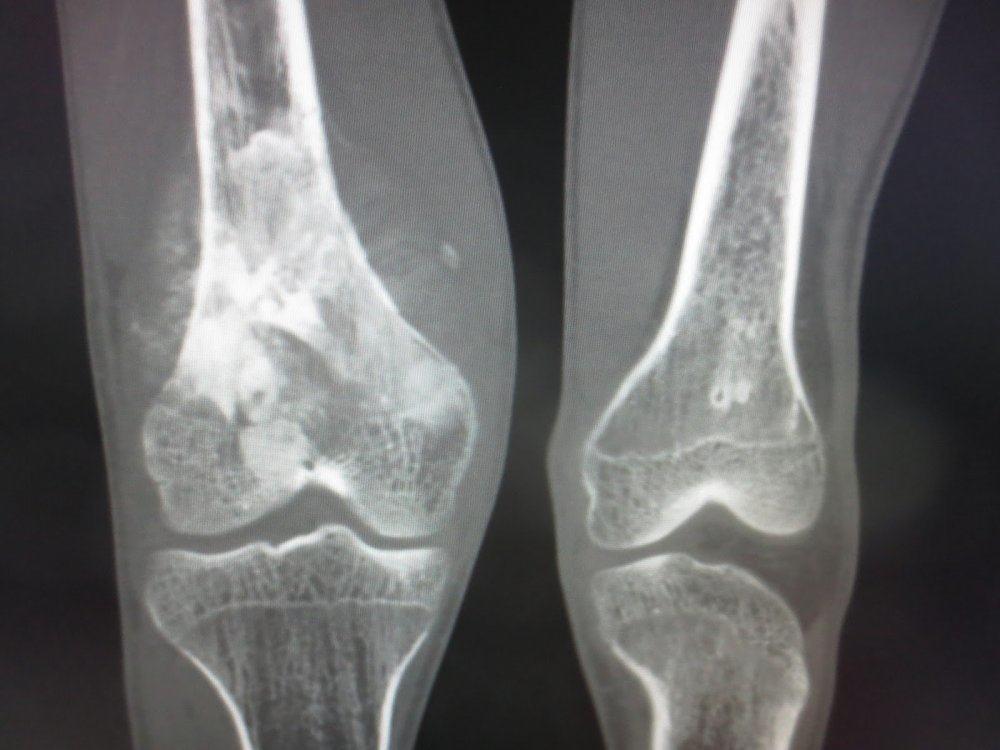

Osteosarcoma merupakan jenis kanker tulang primer yang awalnya terjadi pada sel pembentuk tulang. Penyakit ini kerap menyerang anak-anak dan remaja.

Kebanyakan kasus osteosarcoma ditemukan pada laki-laki daripada perempuan. Tumor umumnya menyerang tulang kering, tulang paha, dan tulang lengan atas.